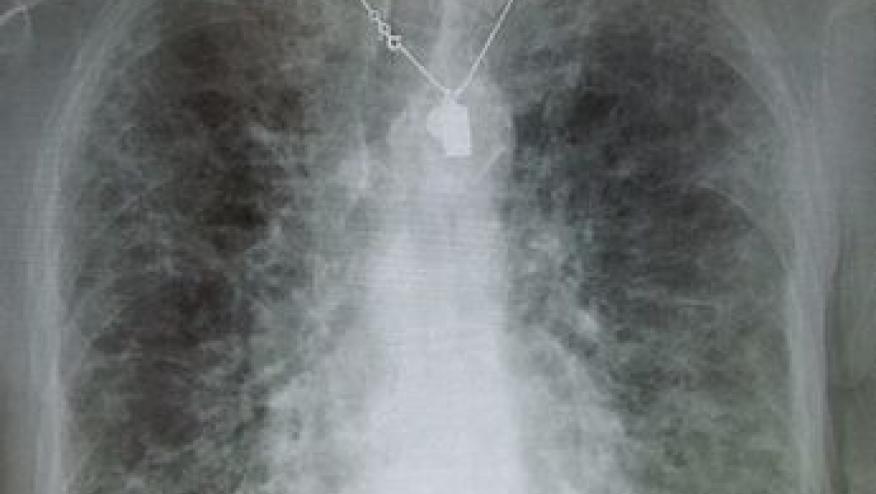

The Wall Street Journal reports that new drug development offers hope for people with idiopathic pulmonary fibrosis, a rare, progressive fibrosing lung disorder that affects nearly 200,000 Americans, mostly middle-aged and older adults.